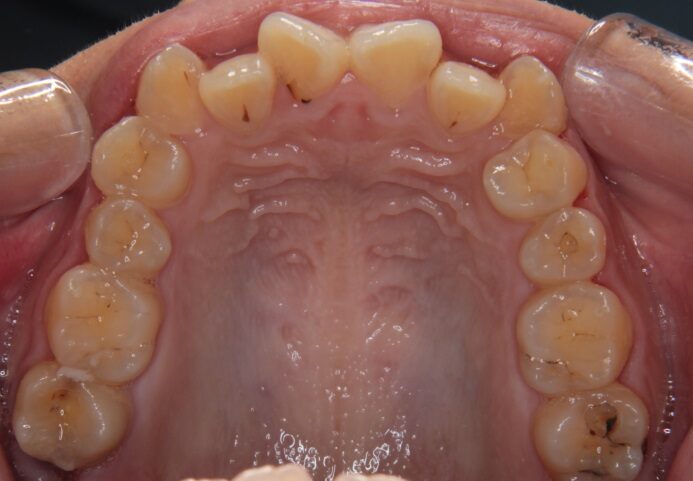

症例情報

主訴 八重歯を凸凹した歯並びが気になる

診断名 上下顎前歯の重度叢生症例

年齢 13歳

治療に用いた装置 マルチブラケット装置

抜歯部位 上顎左右4番、下顎左右4番

治療期間 35回・3年半

治療費用 880,000円

リスク・副作用

• ブラケット装着によるカリエスリスクの上昇